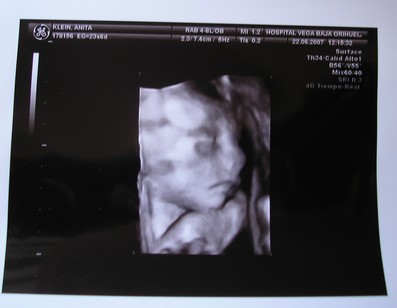

Ma kora reggel megszülettek a kicsi fiúk, róluk hoztam képeket nektek. Éjfél körül szivárgott a huginál a magzatvíz, felhívták a kórházat, ott mondták, inkább menjenek be, az a biztos. Kapott antibiotikumokat, de sajnos beindult a szülés. 4.32-kor megszületett a Bálint, 1990gr és 44cm, valmint 4.39-kor a Kristóf 2170gr és 44cm. Valami tüdősegítő oxigént kapnak, a Bálintnak sűrű volt a vére, de úgy néz ki, hogy helyre áll magától. Amint megindul a teje kiveheti őket szoptatni, talán 1 hetet kell bent lenni.

Kép

Ő pedig a Bálint.